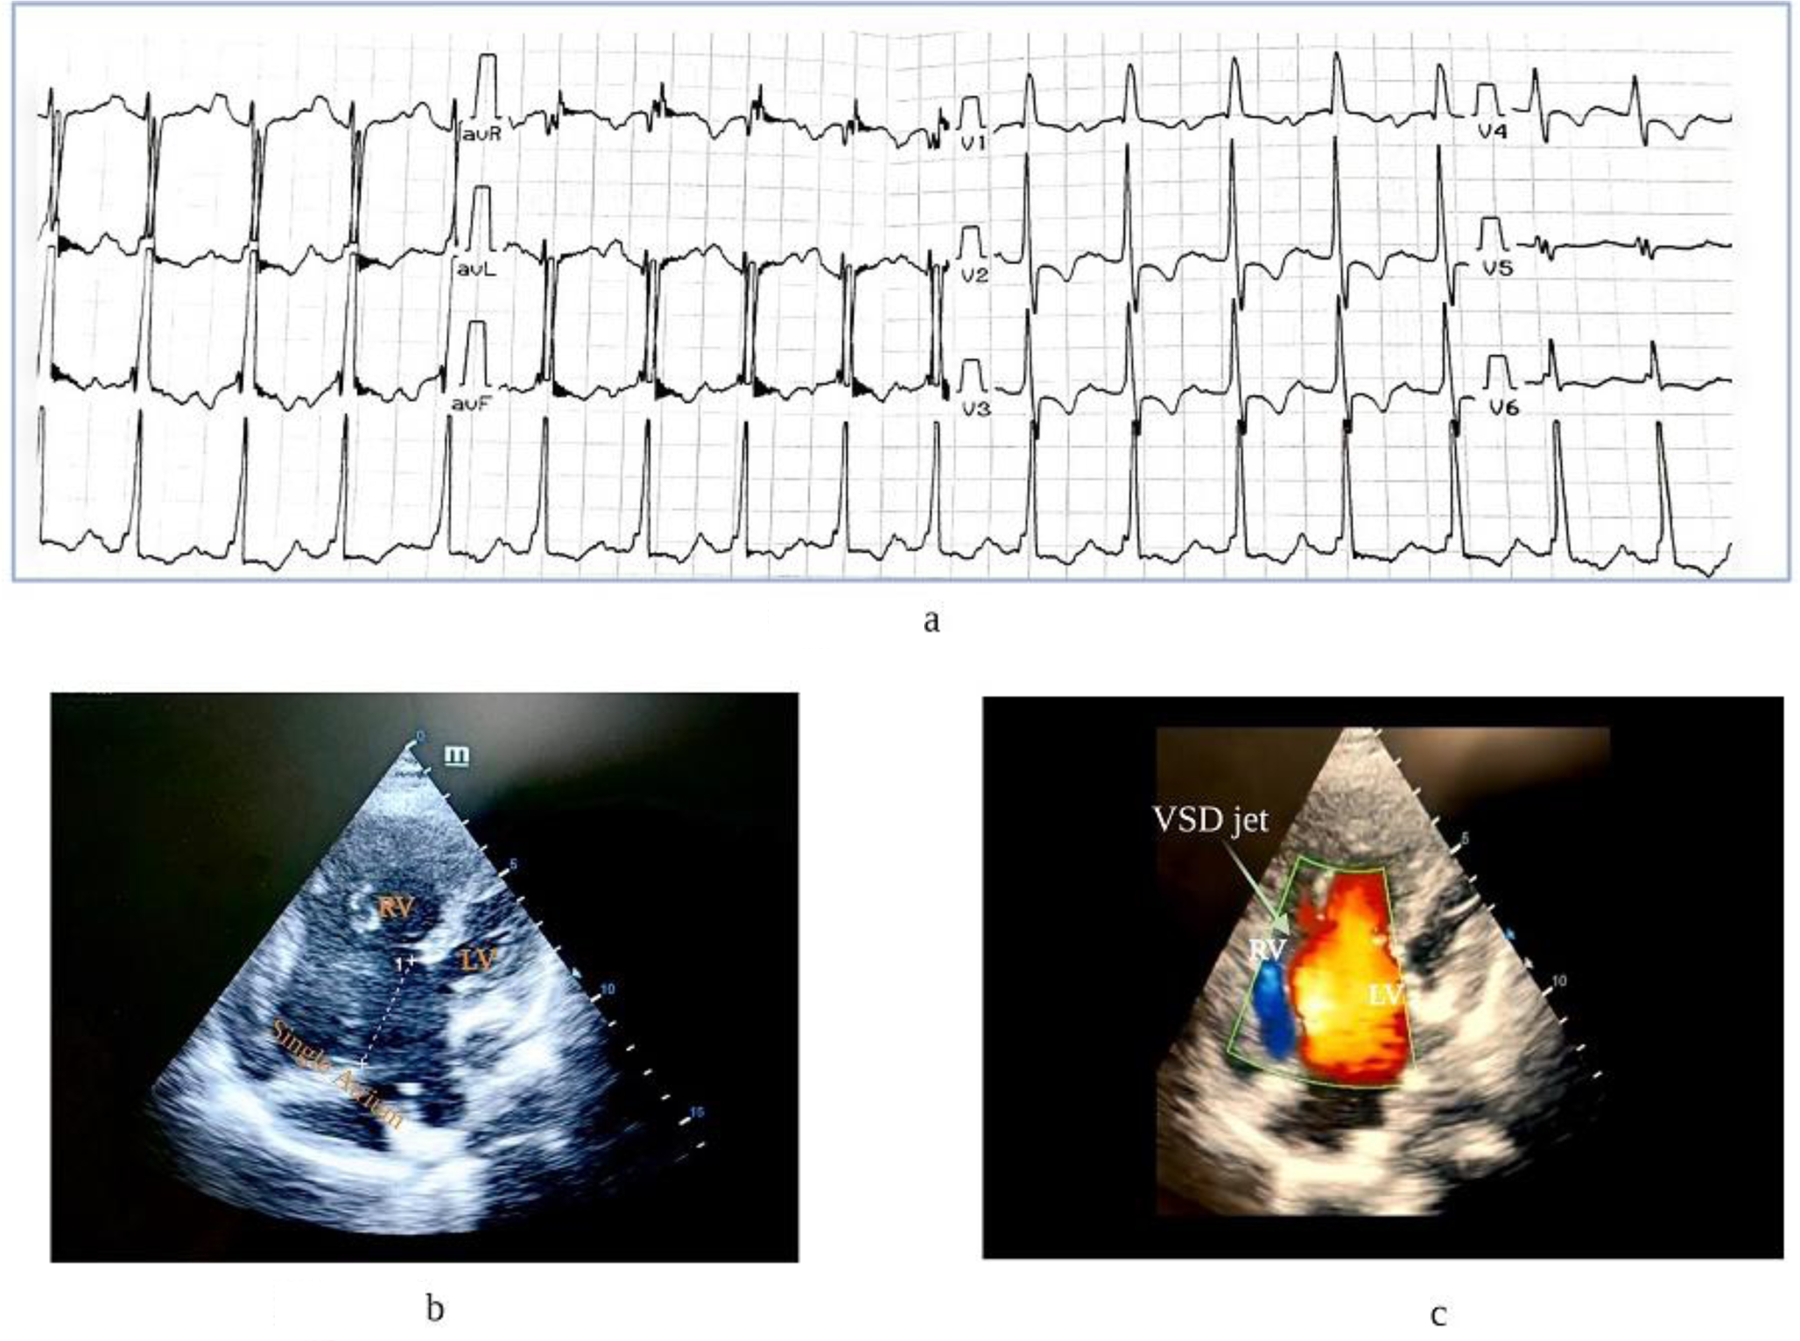

Case presentation: We present the case of a 25-year-old female patient without any family history of Brugada syndrome nor related congenital cardiovascular disorders, with an extensive atrioventricular canal defect, who tested positive for a novel heterozygous variant NM_198056.3: c.3169G>C (p. Asp1057 His) in the SCN5A gene. She had no history of syncope or aborted sudden cardiac death except for recurrent chest infections since her early childhood. Intriguingly, she did not show a type I Brugada electrocardiogram pattern.